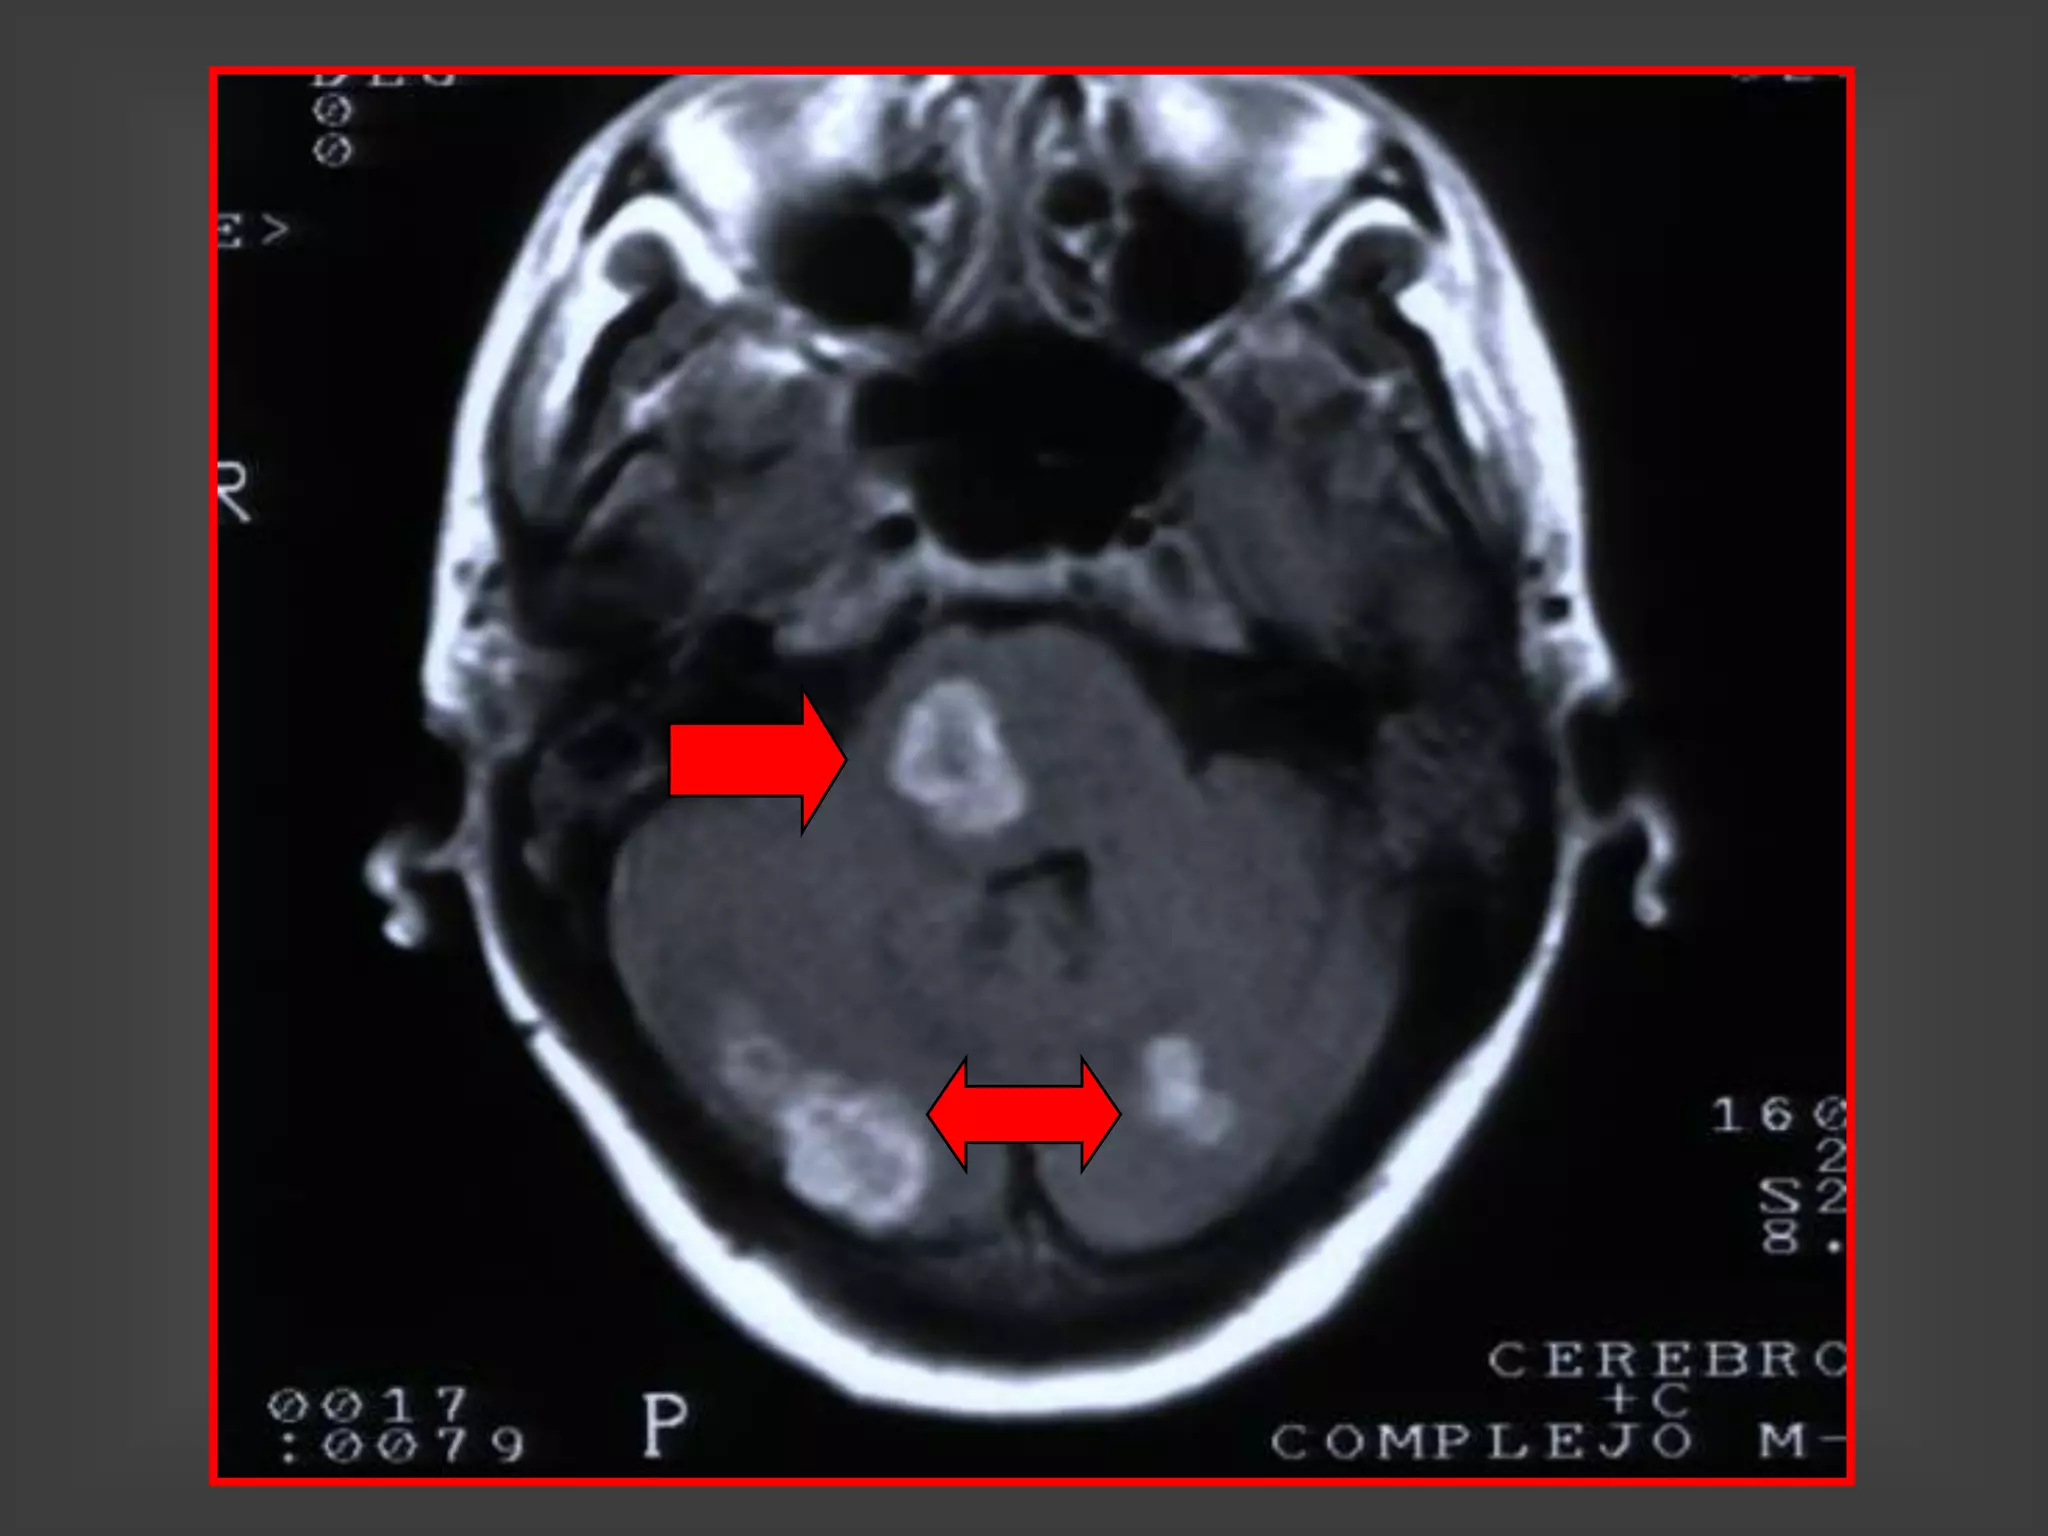

TOXOPLASMOSIS FOSA

POSTERIOR

TOXOPLASMOSIS DE FOSA

TOXOPLASMOSIS CEREBRAL-SIDA

HALLAZGOS EN LAS NEUROIMÁGENES

1. Lesiones hipodensas con refuerzo en anillo y edema

perilesional

2. Lesiones hipodensas sin captación del contraste con

edema perilesional

3. Lesiones nodulares (toman el contraste en forma

homogénea) y edema perilesional

4. Edema cerebral localizado sin lesiones focales visibles

5. TAC sin lesiones y RNM con lesiones focales

1 y 3: 80% a 90% de las lesiones